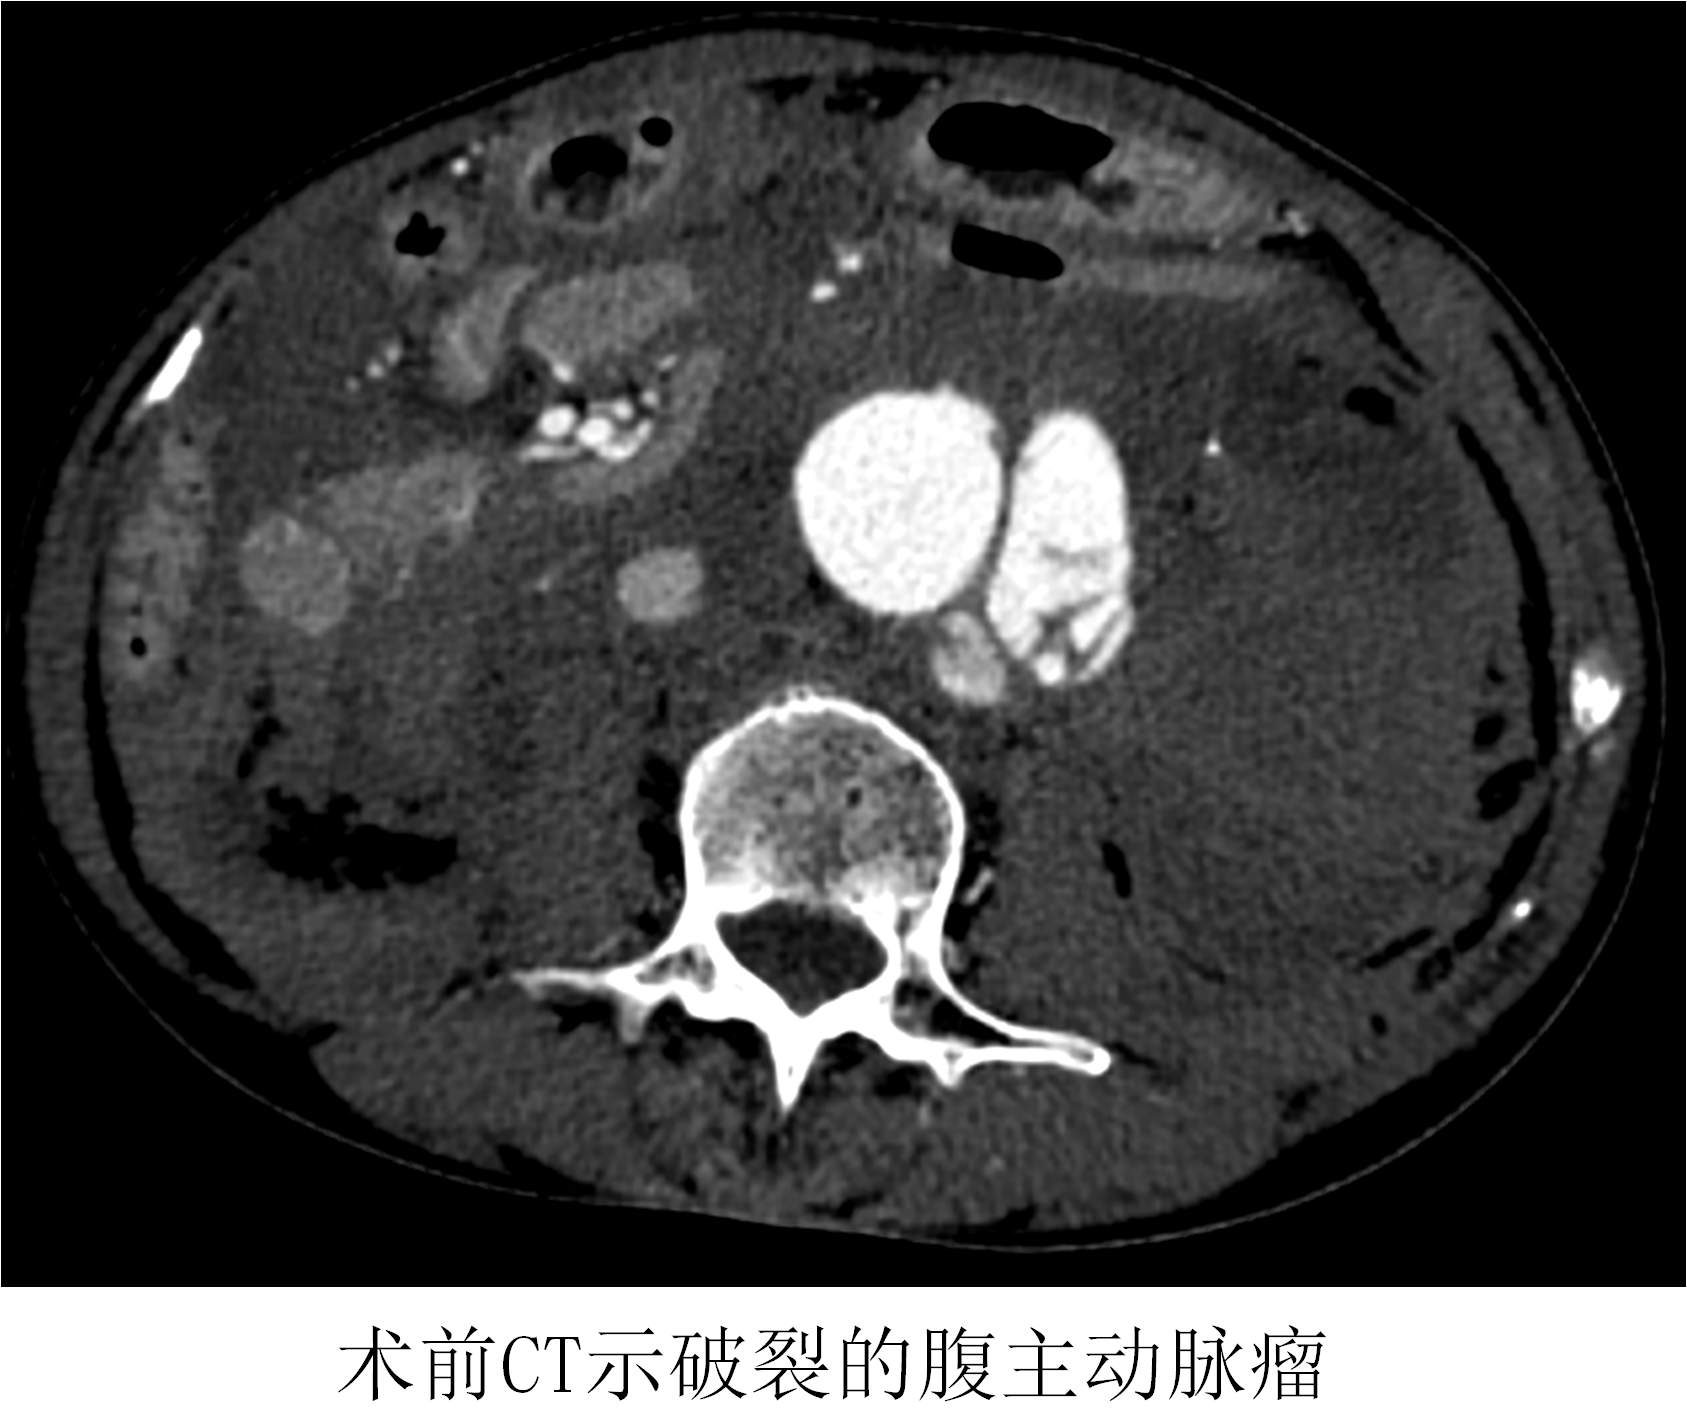

薛冠華在得知患者情況后,立刻從家中趕往醫(yī)院,開始了這場與死神的賽跑。患者在急診抗休克治療的同時(shí),半小時(shí)內(nèi)完成所有檢查,隨即被送入復(fù)合手術(shù)室。此時(shí)患者的血壓繼續(xù)下降,最低時(shí)只有60/30mmHg。

時(shí)間就是生命!在來不及全麻的情況下,薛冠華當(dāng)機(jī)立斷,局麻手術(shù)。手術(shù)由薛冠華主刀、倪其泓和王預(yù)立醫(yī)師共同協(xié)助,在麻醉醫(yī)師黃丹、手術(shù)室護(hù)士夏悅和放射科技師馬鋆的配合下緊張進(jìn)行。薛冠華通過精準(zhǔn)定位,在避免影響內(nèi)臟血管的同時(shí),采用腔內(nèi)技術(shù)在短短30分鐘內(nèi)就將腹主動(dòng)脈瘤的破口通過覆膜支架封堵,有效阻止了進(jìn)一步出血。患者的血壓開始回升,情況逐漸平穩(wěn),手術(shù)順利完成。患者轉(zhuǎn)入重癥監(jiān)護(hù)室后意識(shí)慢慢恢復(fù),術(shù)后10天復(fù)查CT顯示破裂的腹主動(dòng)脈瘤隔絕良好,已于近期康復(fù)出院。